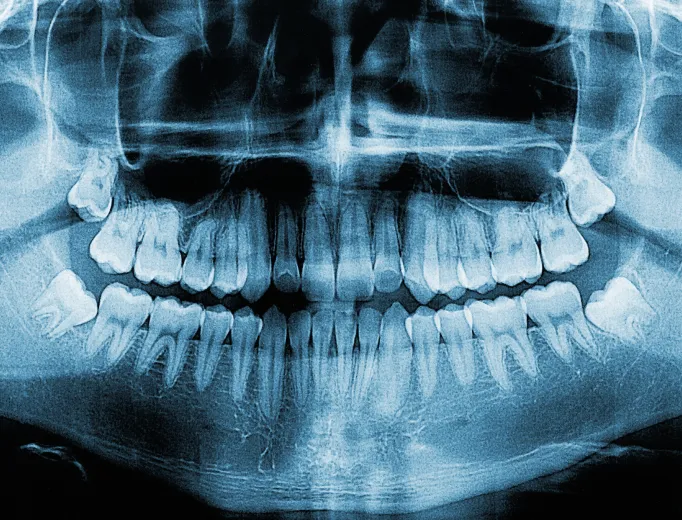

Digital X-rays have transformed the way our dentists diagnose and treat oral health conditions. Unlike traditional film X-rays, digital radiography utilizes a small electronic sensor to capture highly detailed images of your teeth and supporting structures. This modern approach enhances accuracy, reduces radiation exposure and provides instant results, allowing for more efficient and precise diagnoses.

Digital X-rays allow our dentists to detect a variety of dental concerns with enhanced clarity. These images can be enlarged, sharpened and adjusted to reveal issues that might not be visible during a standard examination. Digital radiography is useful in identifying and diagnosing conditions such as:

- Cavities between teeth

- Bone loss associated with periodontal disease

- Infections in tooth roots or nerves

- Developmental abnormalities

- Cysts, abscesses and tumors

- Fractures or damage to existing restorations

By catching dental problems early, we can recommend appropriate treatment before your oral health worsens, helping you maintain a healthier smile.

Digital X-rays play a vital role in planning various dental procedures, including root canal therapy, dental implants, orthodontic treatments and oral surgery. By providing a detailed view of your teeth and jaw, digital radiography helps ensure successful treatment outcomes.